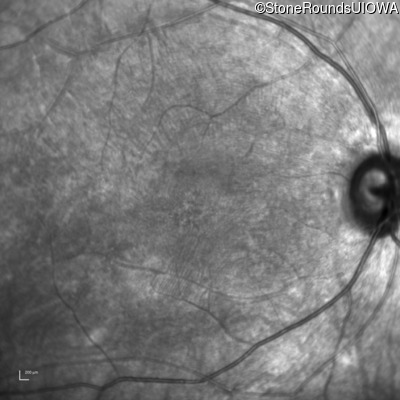

Infrared Fundus Photograph - Left - 20/125 -1 sc

Exemplar